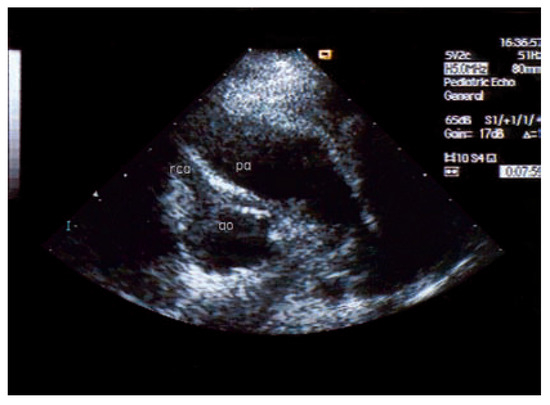

Asymptomatic Bland-White-Garland Syndrome in a 13-Year-Old Girl

by Jean-Pierre Pfammatter, Mladen Pavlovic and Stephan Windecker

An otherwise healthy 13-year-old girl was referred to the pediatric cardiology outpatient clinic for evaluation of a newly observed systolic murmur [...] Full article

Show Figures

Figure 1